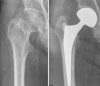

Background: Femoral neck fractures in the elderly are frequent, represent a great health care problem, and have a significant impact on health insurance costs. Reconstruction options using hip arthroplasty include unipolar or bipolar hemiarthroplasty (HA), and total hip arthroplasty (THA). The purpose of this review is to discuss the indications, limitations, and pitfalls of each of these techniques.

Results: THA yields the best functional results in patients with displaced femoral neck fractures with complication rates comparable to HA. THA is beneficially implanted using an anterior approach exploiting the internervous plane between the tensor fasciae latae and the sartorius muscles allowing for immediate full weight-bearing. Based on our findings, bipolar hemiarthroplasty, similar to unipolar hemiarthroplasty, cannot restorate neither anatomical nor biomechanical features of the hip joint. Therefore, it can only be recommended as a second line of defense-procedure for patients with low functional demands and limited live expectancy.

Conclusions: THA is the treatment of choice for femoral neck fractures in patients older than 60 years. HA should only be implanted in patients with limited life expectancy.